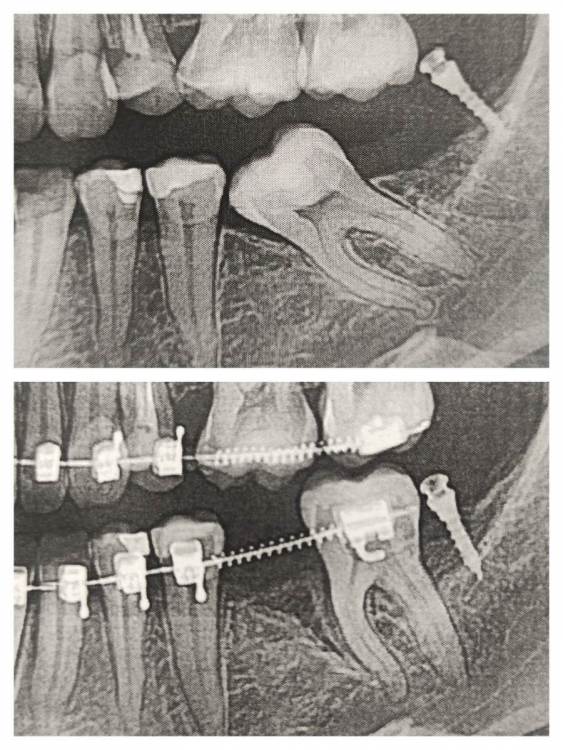

Луиза Николаевна Опубликовано 12 сентября, 2022 Автор Поделиться Опубликовано 12 сентября, 2022 (изменено) Ещё вопрос уважаемые доктора! Мог ли нерв стать таким суровым, если это был лежачий зуб и его передвигали? Прилагаю фото с разницей +- полгода. Нужно ли терапевту говорить об этом передвижении?.... Изменено 12 сентября, 2022 пользователем Луиза Николаевна Ссылка на комментарий

Afffinity Опубликовано 12 сентября, 2022 Поделиться Опубликовано 12 сентября, 2022 48 минут назад, Луиза Николаевна сказал: Ещё вопрос уважаемые доктора! Мог ли нерв стать таким суровым, если это был лежачий зуб и его передвигали? Прилагаю фото с разницей +- полгода. Нужно ли терапевту говорить об этом передвижении?.... Наклон зуба абсолютно не при чем. 1 Ссылка на комментарий